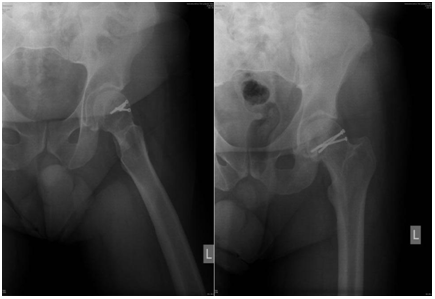

The patient at the age of 34 and 150kg of body weight suffered left hip posterior dislocation with femoral head fracture in car crash accident. The patient had been admitted to hospital after midnight. The mechanism of injury goes as follows: axial force and flexion in the hip caused by impact of the car. The left leg clinically observed is in painful extension, with minimal movement, strong pain and shortened leg. X-rays shows posterior hip joint dislocation and fracture of the femoral head. Closed reduction under anesthesia was unsuccessful. 3D CT reconstruction that had been taken before proceeding to open procedure shows posterior hip dislocation with femoral head fracture above fovea involving weight bearing portion- Pipkin type II fracture dislocation.

Preoperative x-rays, CT scans and 3D CT reconstructions in emergency department are presented as follows (Figure 1-5).

Figure 1 Preoperative X-ray.

Figure 2 Preoperative CT scans.

Figure 3 Preoperative CT scans.